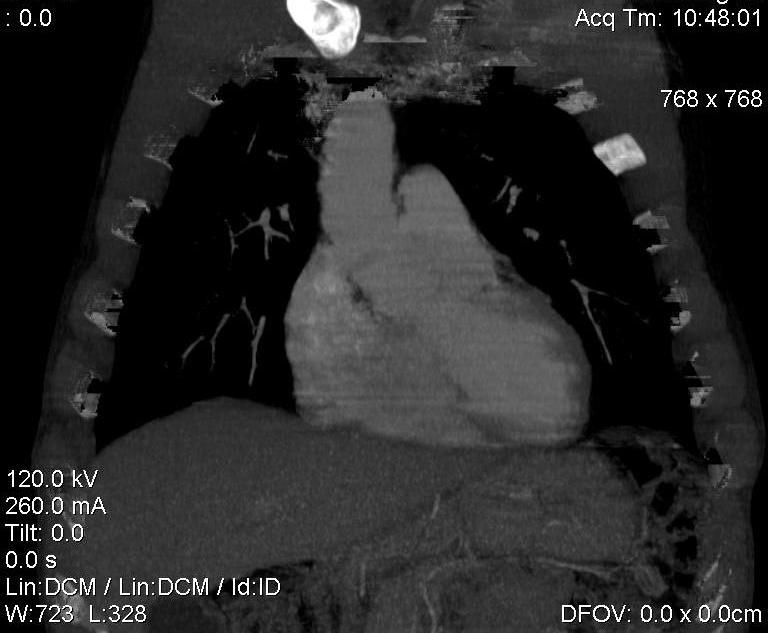

Конечно, дуга аорты идёт справа от позвоночника (декстра позиция); но есть и ещё одна аномалия той же группы: